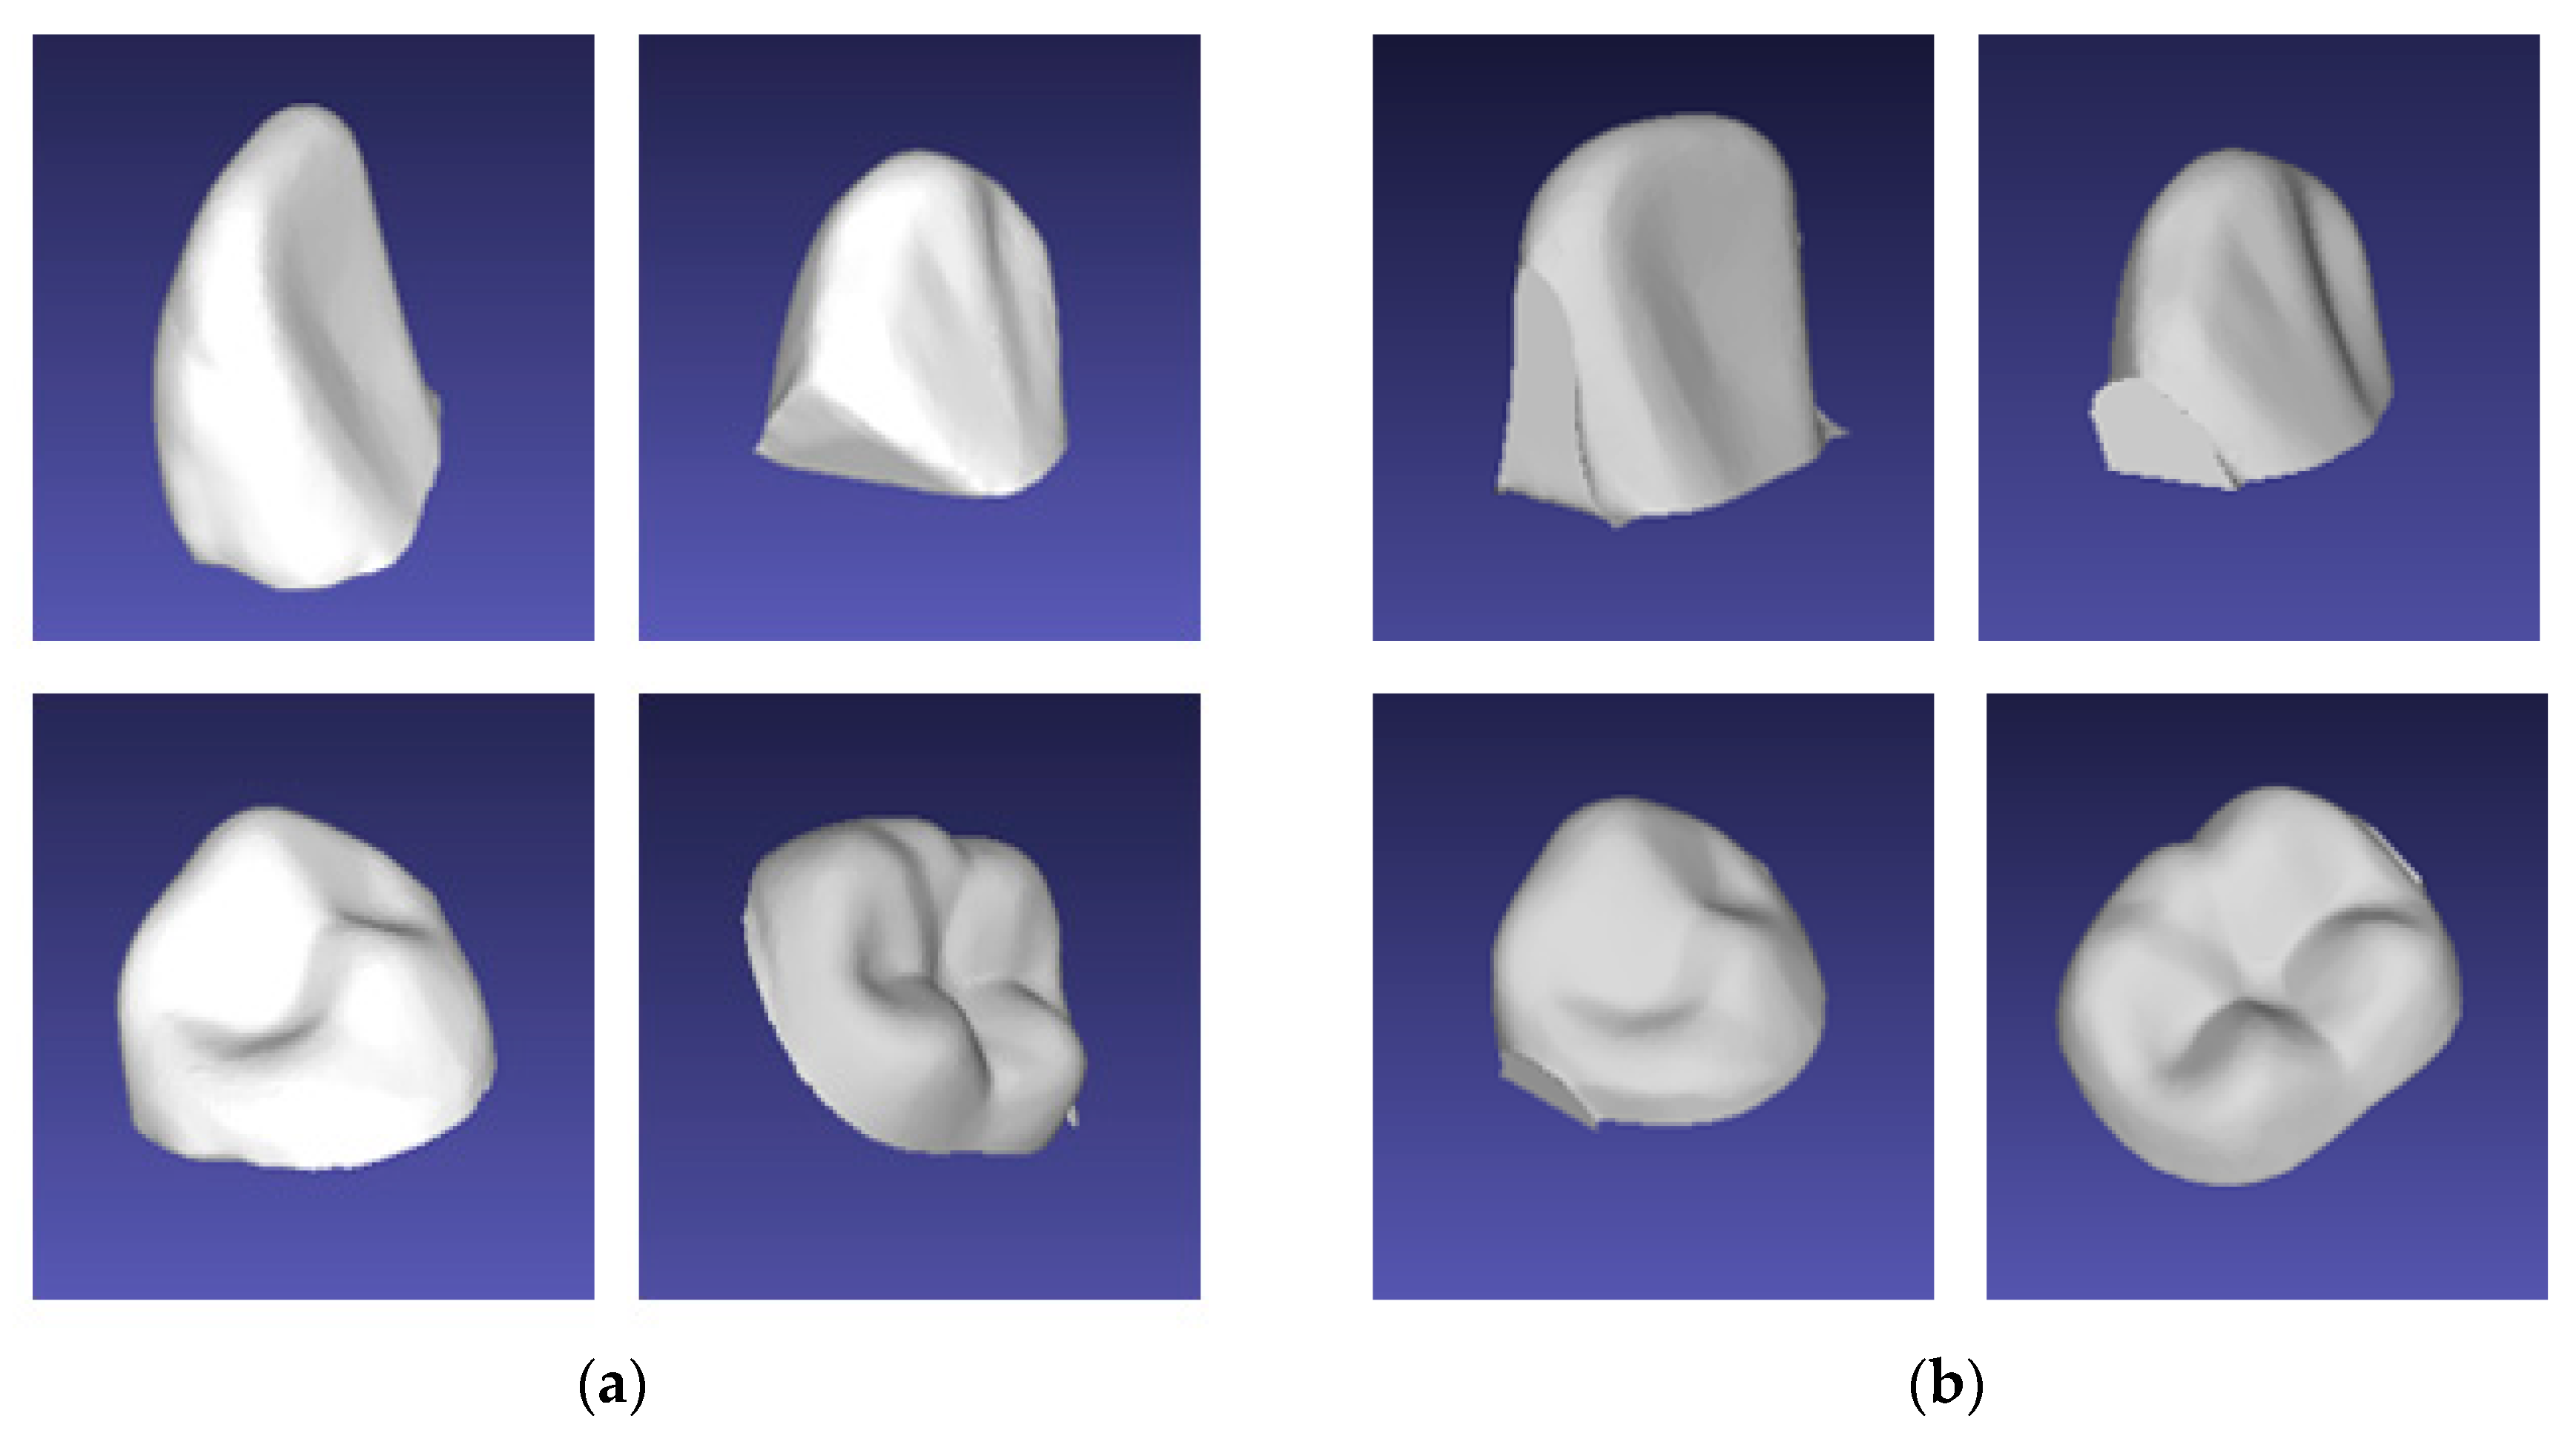

3.2.1. Tooth Model

3.2.2. Accuracy Measurement Process

3.2.3. Measurement Accuracy Results